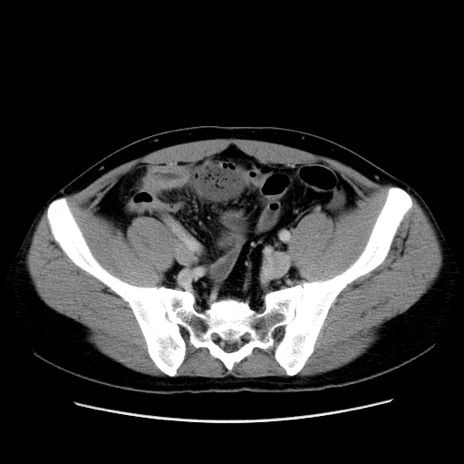

症例4(横断像)

【症例】30歳代男性

【主訴】腹痛、嘔吐

【現病歴】昨晩から突然の腹痛あり、その後嘔吐、軟便も出現。腹痛が改善しないため救急搬送となる。2日前にしめ鯖の食事歴あり。

【身体所見】意識清明、苦悶様、BP 135/90mmHg、BT 35.7℃、腹部:平坦、やや硬、心窩部〜臍部に自発痛、圧痛あり、筋性防御+、反跳痛-

【データ】WBC 8100、CRP 0.57